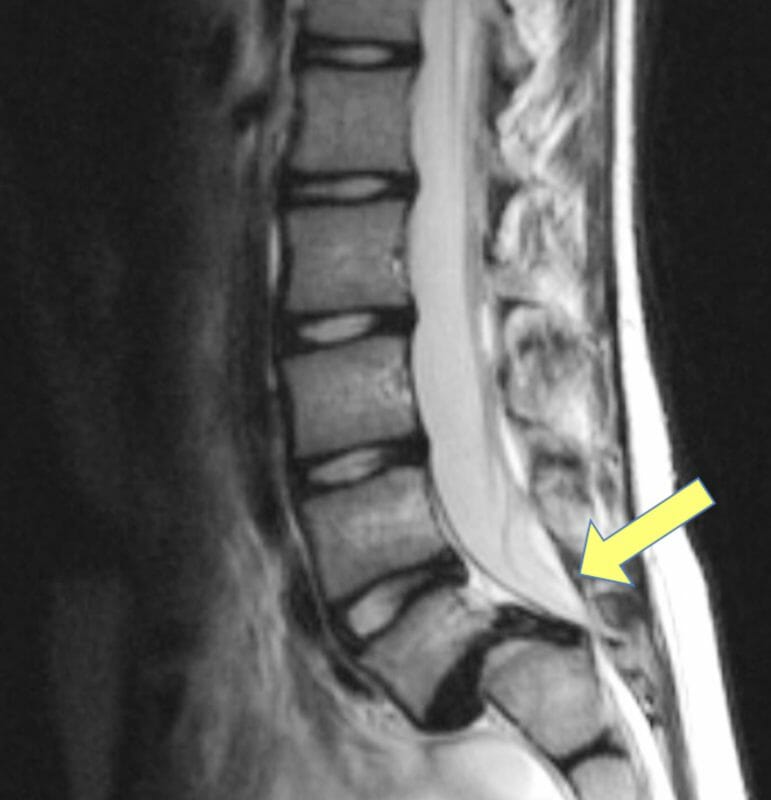

MRI ในผู้ป่วยหมอนรองกระดูกสันหลังเคลื่อน

- การถ่ายภาพ MRI จะสามารถมองเห็นส่วนประกอบที่เป็นเนื้อเยื่อบริเวณรอบกระดูกสันหลังได้ เช่นหมอนรองกระดูก เส้นประสาท กล้ามเนื้อและเส้นเอ็น

- สามารถมองเห็นหมอนรองกระดูกที่เคลื่อนไปกดทับเส้นประสาทได้ เพื่อนำไปช่วยการตัดสินใจวางแผนผ่าตัด